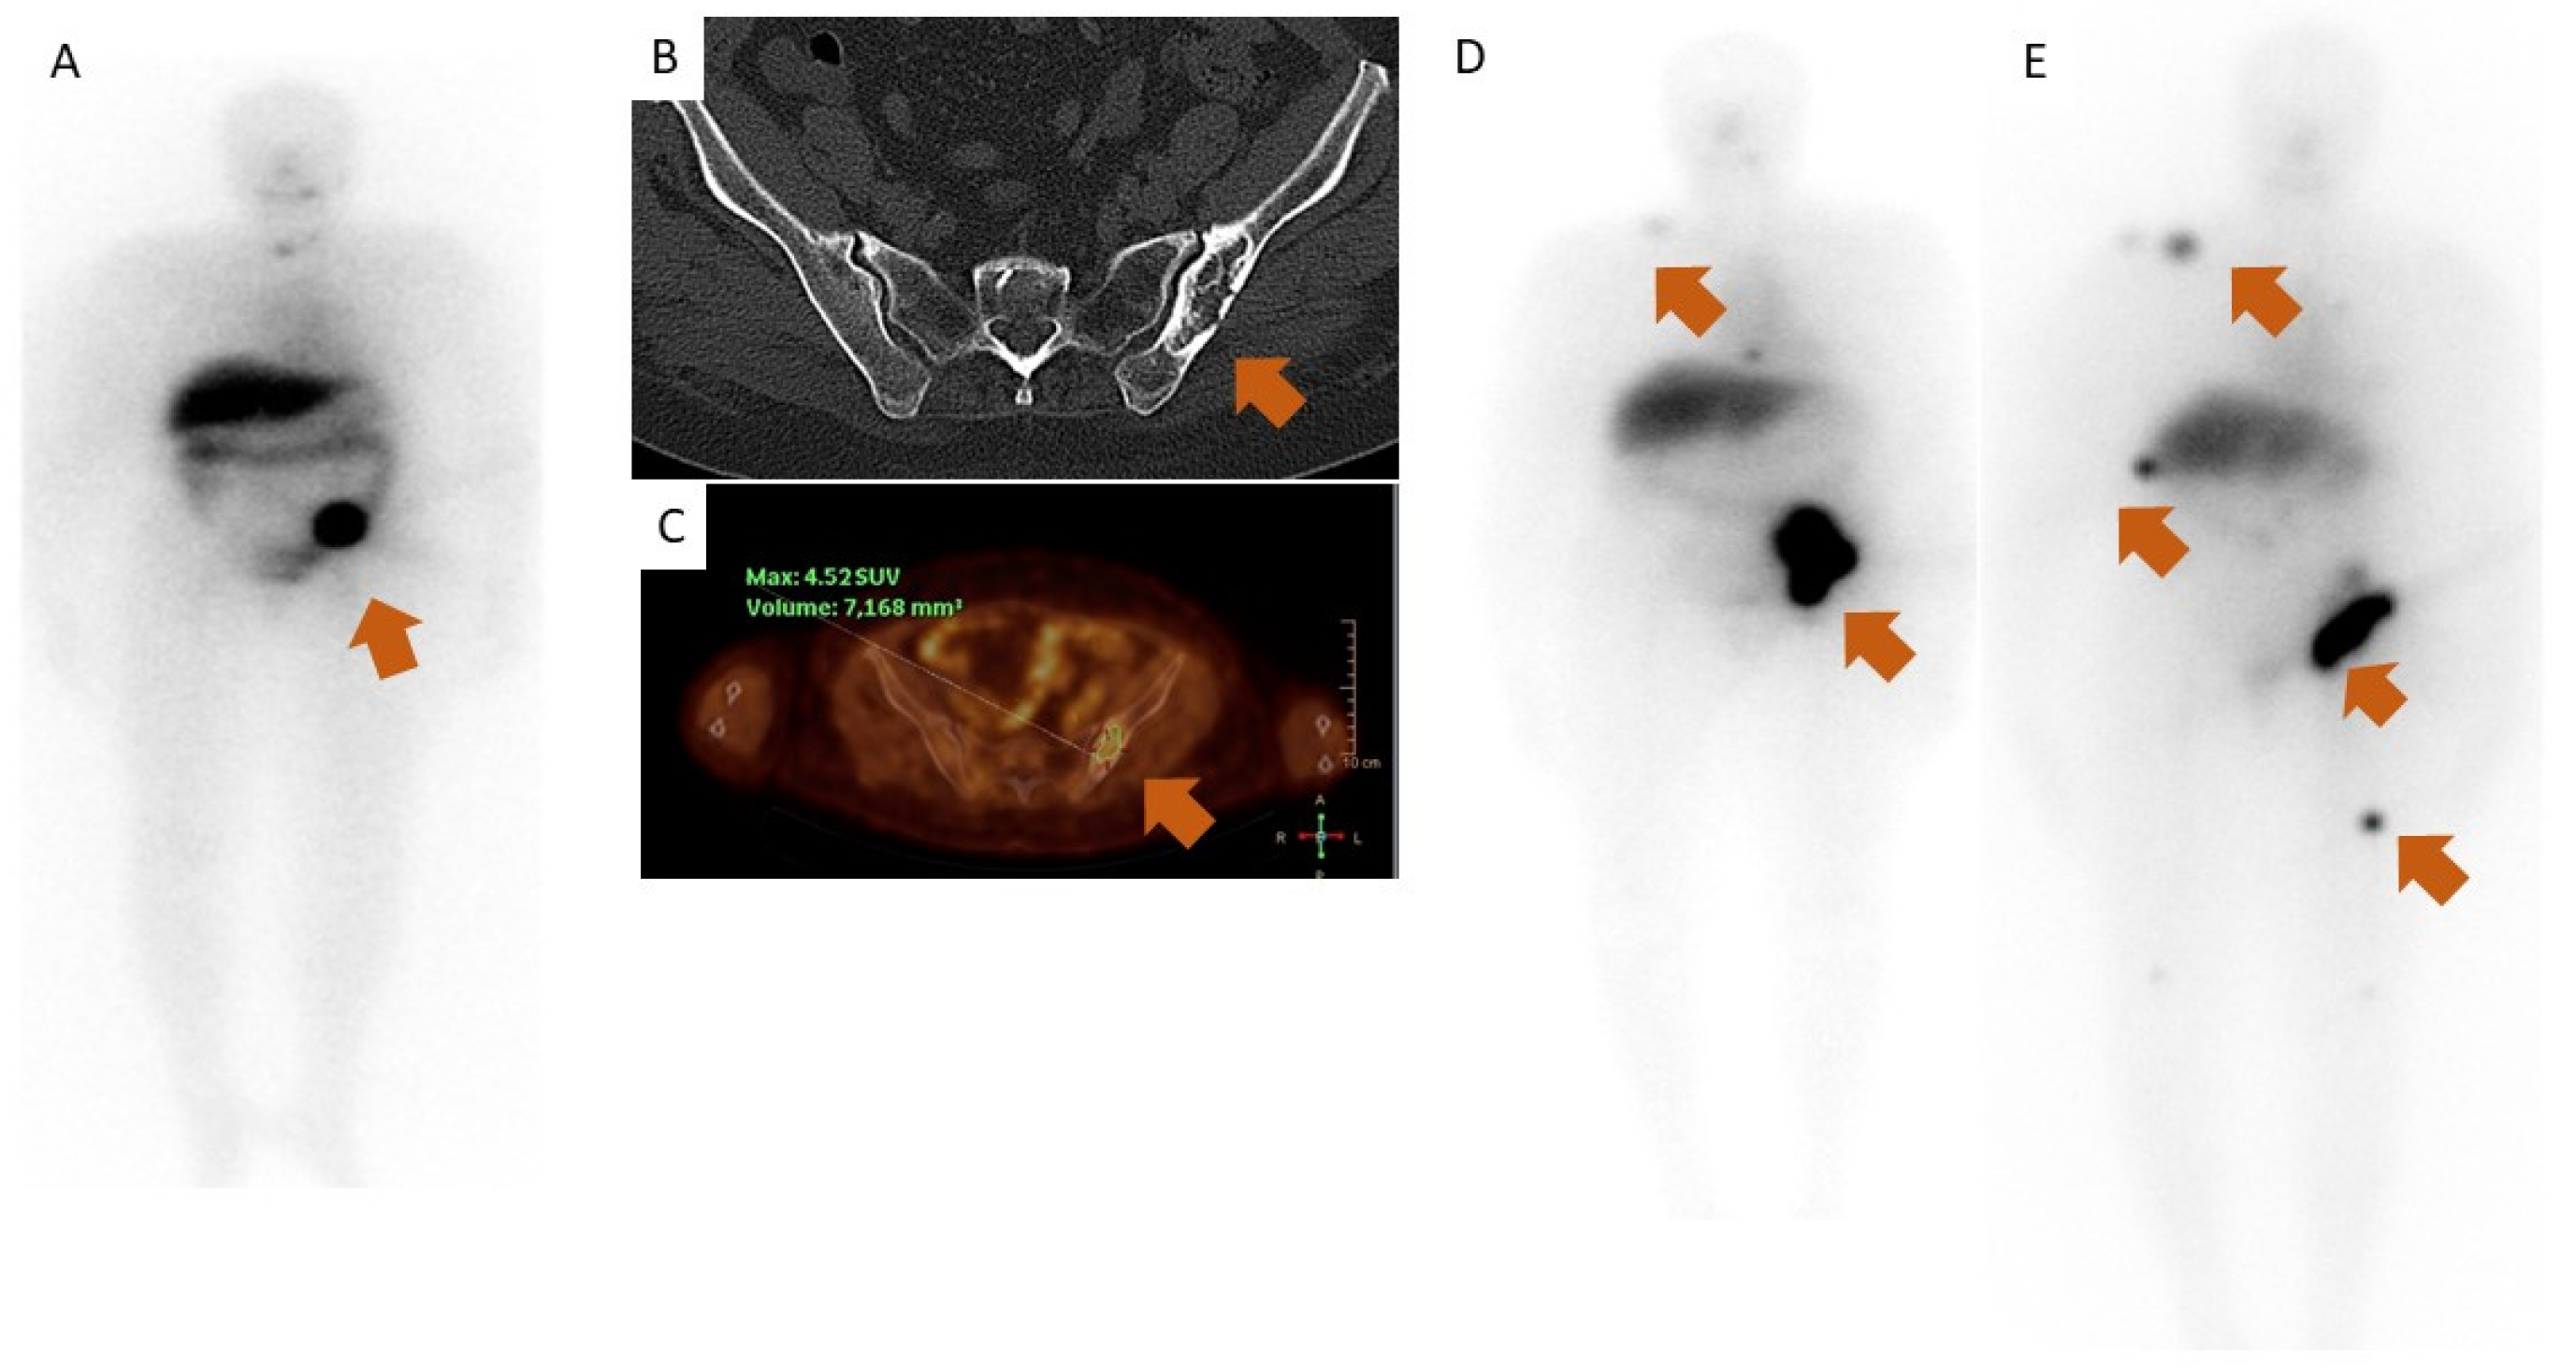

Diagnostics Free FullText Delayed Presentation of Functioning Selenium Cancer Metastasis The major focus of this mini review was to summarize: Collectively, our results identify a vulnerability of cancer cells and define the role of selenium metabolism in cancer. The pathways of selenium metabolism; Recently, a few scientists have examined the relationship between se and metastasis, a late event in cancer progression,. In this chapter, we summarize the current findings indicating. Selenium Cancer Metastasis.